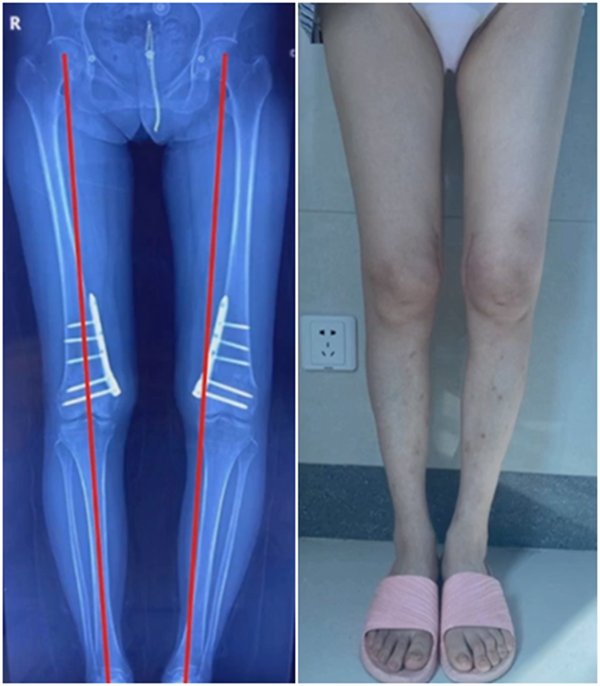

术后10周复查,力线较好。